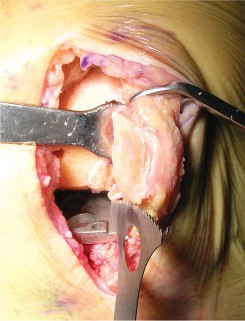

استبدال مفصل الركبة بالإسمنت: تفاصيل العملية

تُعد عملية استبدال مفصل الركبة بالإسمنت إجراءً دقيقًا يتطلب مهارة وخبرة عالية، وهو ما يوفره الأستاذ الدكتور محمد هطيف لمرضاه في صنعاء. تهدف العملية إلى إزالة الأسطح المفصلية التالفة واستبدالها بمكونات اصطناعية (غرسات) تُثبت في مكانها باستخدام إسمنت عظمي خاص.

خطوات العملية الجراحية بالتفصيل

الخطوة 1: التحضير الأولي والوصول إلى المفصل

الخطوة 4: إكمال قطع عظم الفخذ وتحديد الحجم

- نظام التوجيه الخلفي: يُستخدم نظام توجيه خلفي لإكمال قطع عظم الفخذ.

- تحديد الدوران الخارجي: يُحدد المقدار الصحيح للدوران الخارجي لعظم الفخذ بناءً على المحور اللقمي الخلفي، والمحور فوق اللقمتين، وزاوية 90 درجة بالنسبة لمحور الساق (السطح المقطوع)، والمحور الأمامي الخلفي (خط وايتسايد).

- تحديد الحجم: يُوضع الدليل على الجزء البعيد من عظم الفخذ، ويُحدد حجم عظم الفخذ، ويُختار الحجم المطابق للمريض.